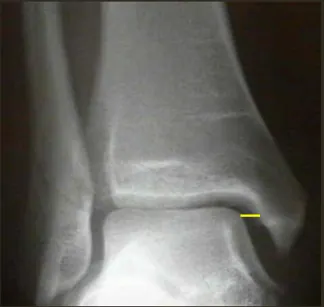

C. Lateral X-ray

Identifies fractures of

Anterior/posterior tibial margins

Talus

Displacement of talus

Os trigonum

Anterior and posterior margins of distal tibia, base of 5th metatarsal bone